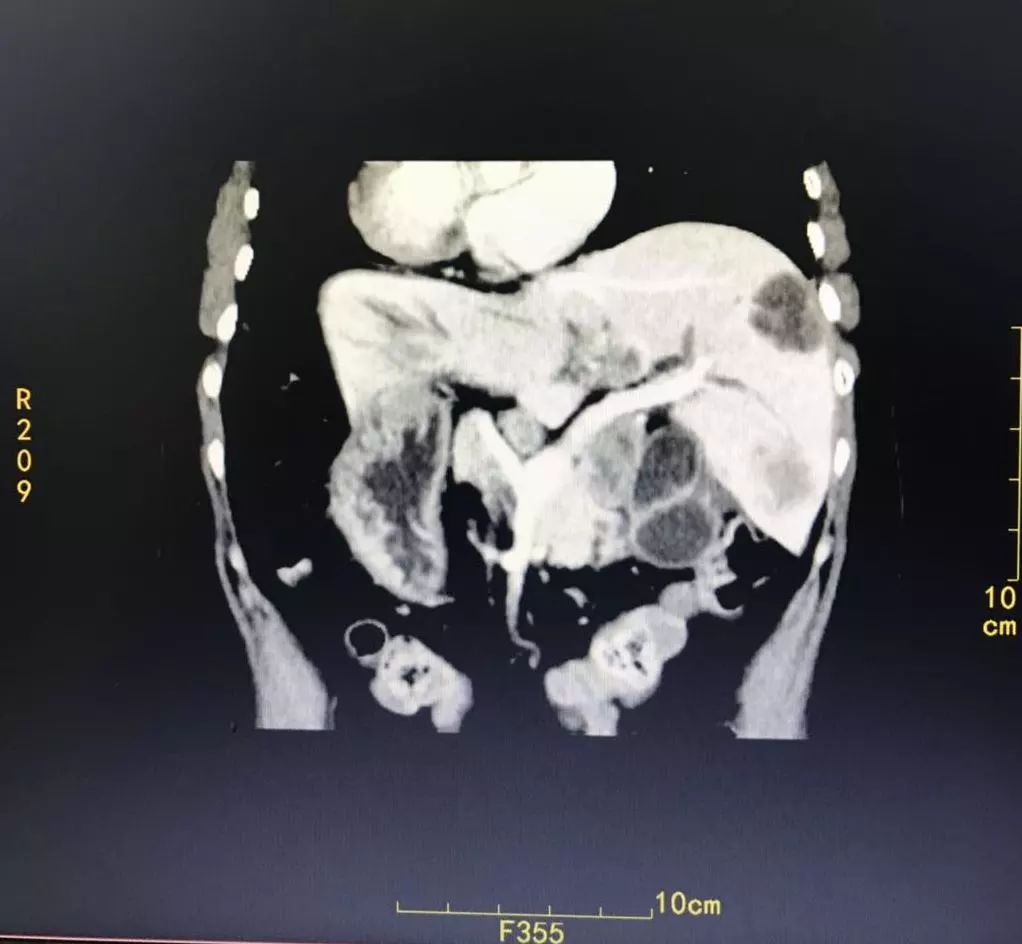

CT提示:胆囊癌伴肝内多发转移